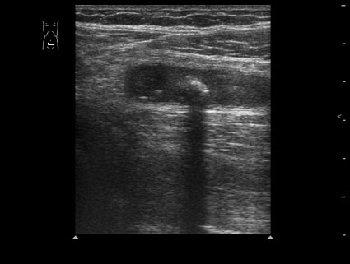

Пациент 32 лет.

В правой подвздошной области определяется утолщенный аппендикс, не компрессируется при надавливании датчиком, в просвете определяется аппендиколит; окружающие аппендикс ткани инфильтрированы.